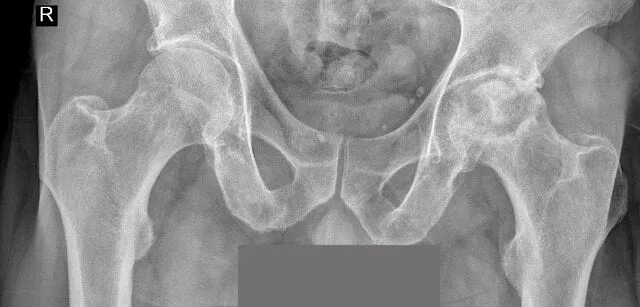

Warto zauważyć, że w przypadku obluzowania endoprotezy mogą wystąpić również inne objawy, takie jak obrzęk wokół stawu, który może być spowodowany uszkodzeniem tkanek miękkich lub samym obluzowaniem protezy. Z czasem mogą pojawić się zmiany radiologiczne, które są widoczne na badaniach obrazowych. Dlatego tak ważne jest, aby monitorować objawy i reagować na nie odpowiednio. Prowadzenie dziennika zdrowia może pomóc w śledzeniu zmian i ułatwić lekarzowi postawienie diagnozy.

Diagnostyka obluzowania endoprotezy stawu biodrowego jest kluczowa dla oceny stanu zdrowia pacjenta i podjęcia odpowiednich działań. W pierwszej kolejności lekarz może zlecić badania obrazowe, takie jak rentgen, które pomagają w ocenie stanu protezy oraz otaczających struktur. W przypadku podejrzenia obluzowania, rezonans magnetyczny (MRI) może dostarczyć bardziej szczegółowych informacji na temat tkanek miękkich i ewentualnych uszkodzeń. Dodatkowo, wykonanie tomografii komputerowej (CT) może być pomocne w ocenie przemieszczenia implantu lub zmian w strukturze kostnej. W niektórych przypadkach lekarz może również zlecić badania laboratoryjne, aby ocenić ogólny stan zdrowia pacjenta oraz wykluczyć infekcje, które mogą wpływać na stan endoprotezy.

| Rentgen | Podstawowe badanie obrazowe, które ukazuje stan kości i protezy. | Ocena przemieszczenia implantu oraz zmian w strukturze kostnej. |